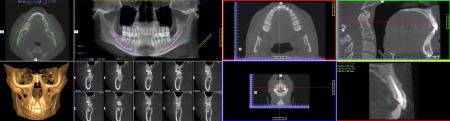

| 最新鋭歯科用CTを設置しております。 |

| 当院ではこれまで以上に正確な診断、安全な治療を行うため、最新式の歯科用CT(コンピュータ断層撮影装置)を導入しております。 |

3次元データによる圧倒的な情報量 |

一般のレントゲンで見えなかった部分が容易に確認できるようになり、さらに正確な診断をおこなうことができるようになりました。

インプラント・矯正・抜歯など幅広い応用が可能で、治療の安全性を飛躍的に高めます。 |